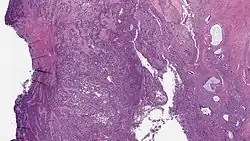

| Micrograph of a low-grade endometrial stromal sarcoma. H&E stain. | |

Low-grade endometrial stromal sarcoma consists of cells resembling normal proliferative phase endometrium, but with infiltration or vascular invasion. These behave less[3] aggressively, sometimes metastasizing, with cancer stage the best predictor of survival. The cells express estrogen/progesterone-receptors.

Microscopy

- Monotonous ovoid cells to spindly cells with minimal cytoplasm.

- Prominent arterioles. Angiolymphatic invasion common.

- Up to 10-15 mitotic figures per 10 HPF in most active areas.

- Tongue-like infiltration between muscle bundles of myometrium.

- May exhibit myxoid, epithelioid and fibrous change.

- May have foam cells or hyalinization in the stroma.